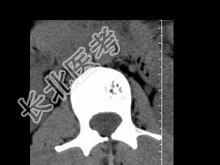

- 单项选择题根据所提供的图像,最可能的诊断 ( )

A、骨结核

B、多发性骨转移

C、骨血管瘤

D、退行性变

E、骨质疏松